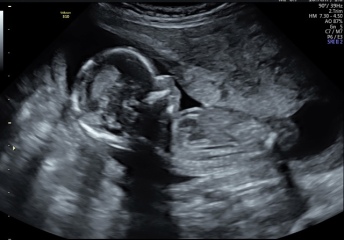

@Cassarat @xalexandra

we found out this morning that it’s… a… GIRL! Soooooo happy can’t believe it still

@Sprinklerainbows omg!!! Congratulations 💕💕💕💕 that's amazing news and love them scan pics, such good ones! She looks like she's doing ok in there 🥰

Sprinklerainbows · 10/12/2022 14:31

@xalexandra ahhh thank you. One of each is the dream for us.

they did a health check and apparently all looks well in there, another anterior placenta (I KNEW IT)

they took a long time deciding the gender so hope it’s right 🤣